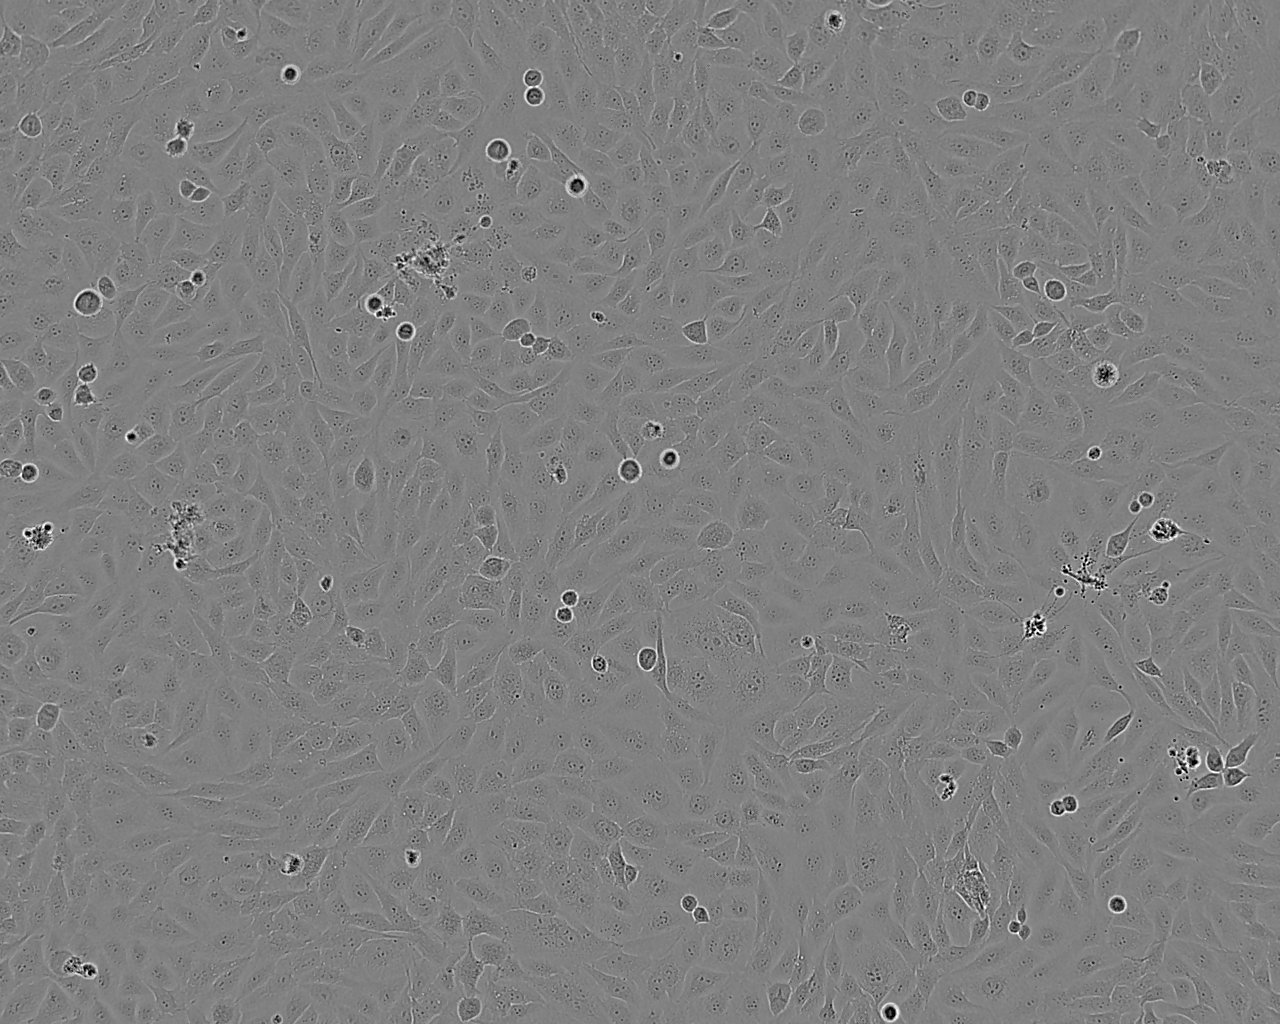

细胞背景资料:SK-OV-3由G.Trempe和L.J.Old在1973年从卵巢肿瘤病人的腹水分离得到。 此细胞对肿瘤坏死因子和几种细胞毒性药物包括白喉毒素、顺铂和阿霉素均耐受。 在裸鼠中致瘤,且形成与卵巢原位癌一致的中度分化的腺癌。

细胞形态:上皮细胞样

细胞生长:贴壁

细胞生长特性:贴壁

细胞形态特性:上皮细胞样